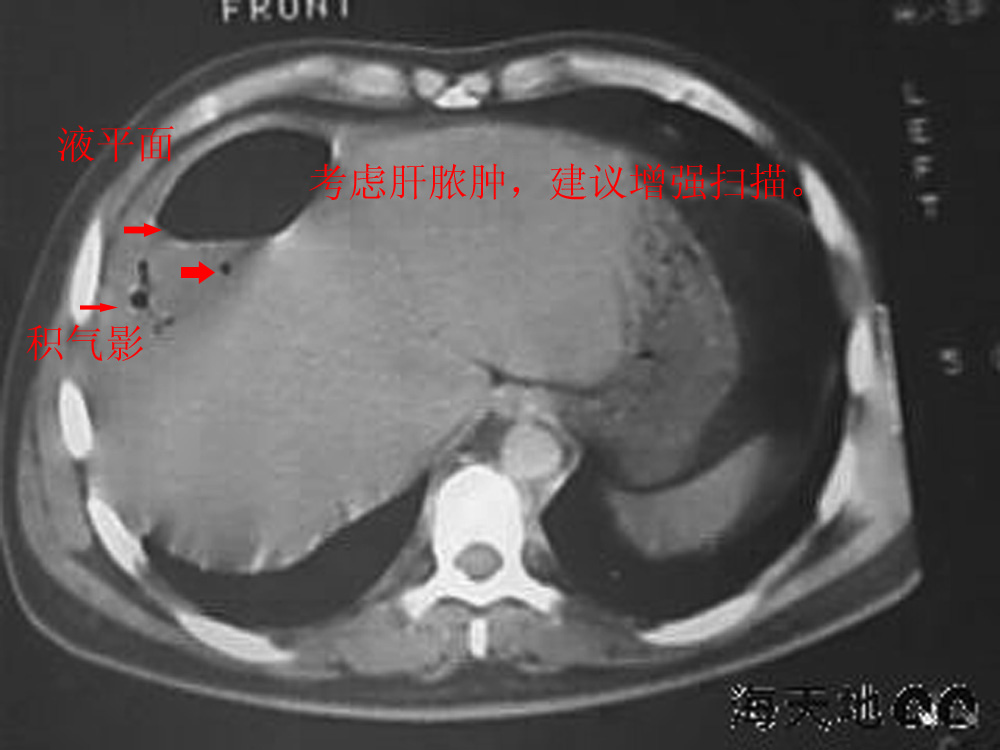

男 32y 外伤后一月余,现 t38.5,肝区隐痛。

右肝膈顶区液气平面.右膈肌增厚改变,病灶下部层面呈半月形延伸于肝表面.且于横结肠无明确密度切关系.

结合临床症状;考虑膈下脓肿.建议薄层矢状重建进一步证实.

鉴别;1,膈疝;2,间位结肠.

右隔肌与肝顶之间隙有长气液平,其下散在点状气体影,右侧腹膜局限增厚。考虑右膈下脓肿。

考虑右膈下脓肿。病灶不在肝内,位于肝外膈下;病灶下方的层面无结肠影与之相连。

右膈肌增厚,肝膈间见条状低密度影内可见积气影及宽大液平面,并未见与结肠相连。因此考虑膈下脓肿。